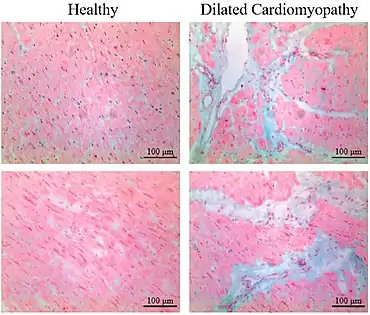

Micrograph of healthy myocardium versus interstitial fibrosis in dilated cardiomyopathy. Alcian blue stain. The fibrosis is either evenly distributed between myocytes or follows anatomic structures such as blood vessels.

Micrograph of healthy myocardium versus interstitial fibrosis in dilated cardiomyopathy. Alcian blue stain. The fibrosis is either evenly distributed between myocytes or follows anatomic structures such as blood vessels. Interstitial fibrosis of chronic ischemic heart disease, H&E stain, with associated relatively well organized myocardial bundles